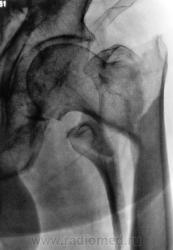

1. Эх, гололёд, гололёд, гололёд...

Опять все обледенело. Травмы, травты, травмы...

Ваше мнение коллеги?